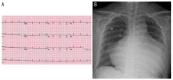

BACKGROUND Thyroid function is closely related to the cardiovascular system. Pericardial effusion is a well-known complication of hypothyroidism. It is common for massive pericardial effusion to progress to tamponed heart with hypotension, but not high blood pressure. CASE REPORT A 46-year-old woman presented to the hospital with dysarthria and left-side weakness of the upper limb which had started 30 minutes before her arrival at the hospital. The patient showed hypertensive emergency (213/124 mmHg) with intracerebral hemorrhage. Further evaluation for high blood pressure and transthoracic echocardiography demonstrated the presence of a large amount of pericardial effusion, and urgent pericardiocentesis was performed. The laboratory examination showed elevated thyroid-stimulating hormone and decreased free thyroxine level, leading to a diagnosis of primary hypothyroidism. The administration of current medications was maintained, including thyroid hormone replacement and anti-hypertensive drugs. CONCLUSIONS A rare case of profound hypothyroidism presenting with hypertensive crisis and massive pericardial effusion is described in this report.